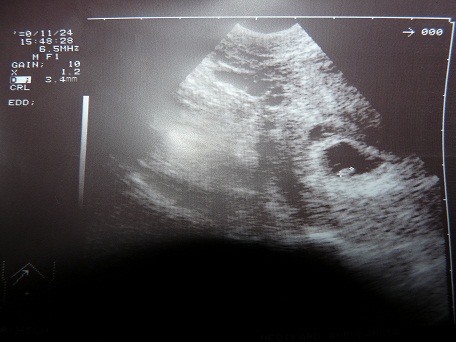

mekkora az a nagyon kicsi? Nekem ennyi idősen még csak petezsákok voltak a gyerekek.

Nálunk a kötelező UH-kat nem is orvos csinálja, hanem erre "szakosodott" szonográfus. Mást el sem fogadnak. Lehet magánban csináltatni, de csak annál, aki a kórházban is csinálná.